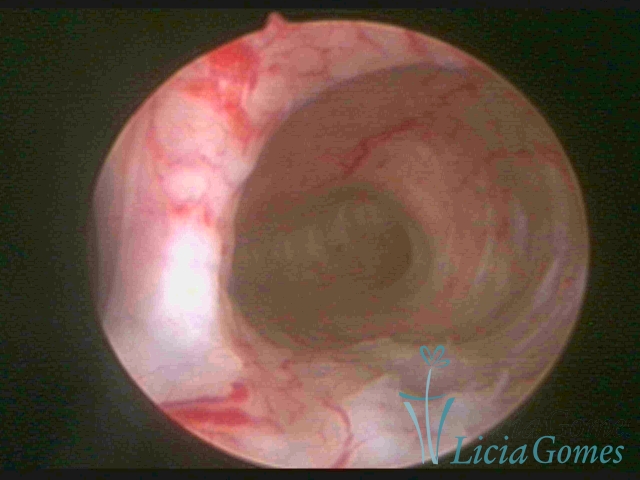

Septate uterus

It probably occurs by the lack of resorption on the middle line, in the merge of Müllerian ducts. The uterus is divided by a partial or total septum which is viewed as a crossbar, not covered by endometrium, which not bleeds when sectioned.

Complete septum when it occupies the whole extension of the cavity, dividing it into two hemicavities.

When this septum occupies only a part of the extension of the uterine cavity, it is considered as incomplete.